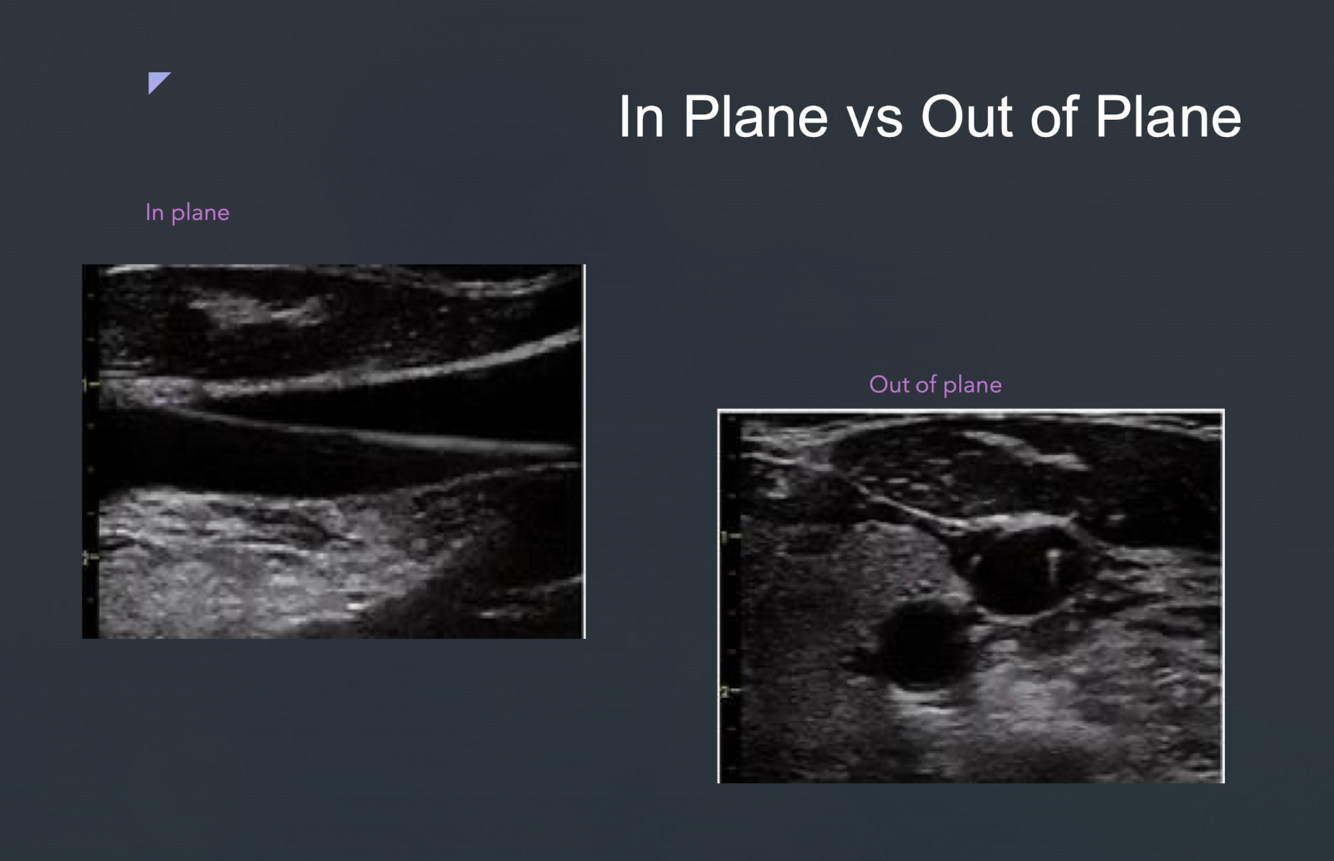

Pic of in plane vs out of plane

A